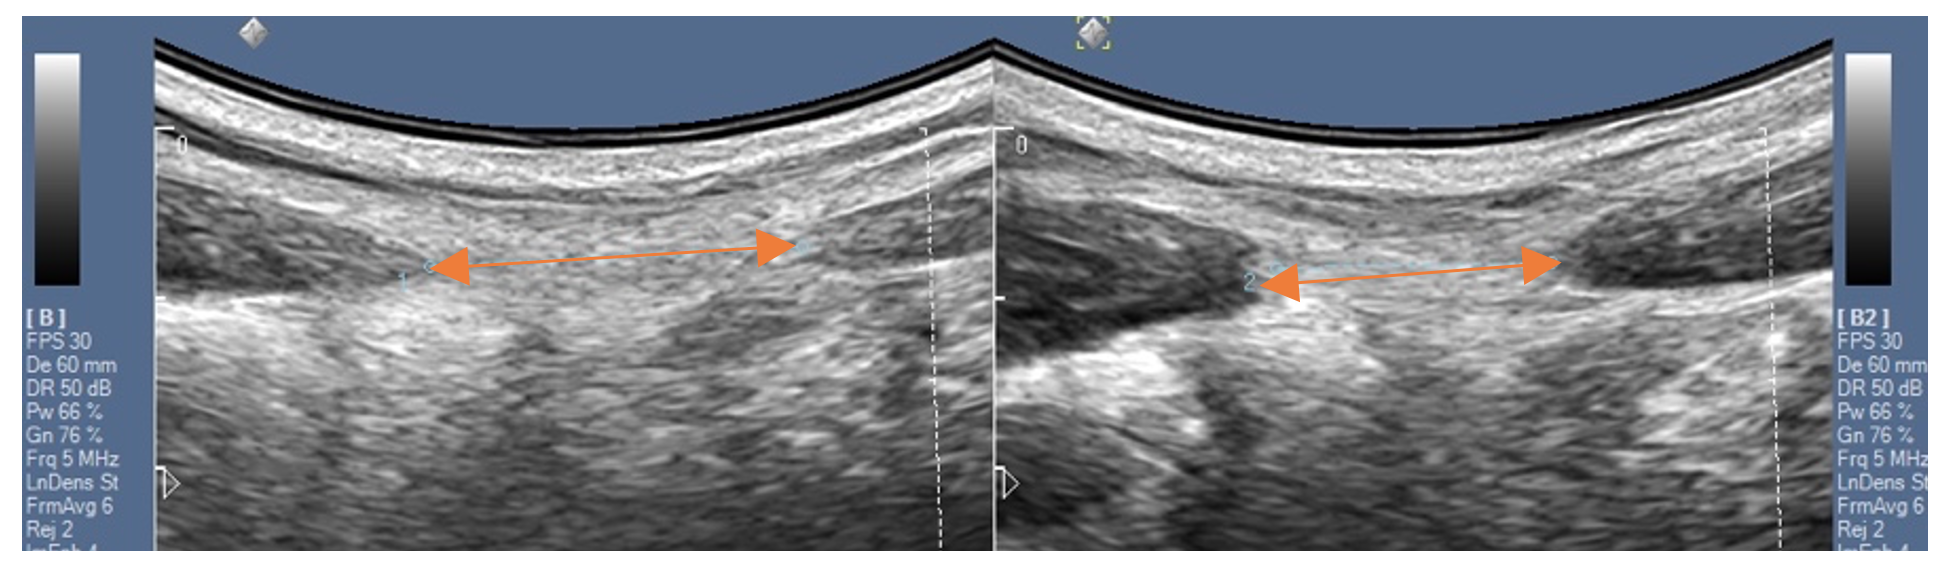

We zullen in het onderzoek oog hebben voor je algehele houding, je ademhaling, je lage rug en bekken. Ook testen we de stabiliteit van je lage rug. Ik kan als bekkenfysiotherapeut al je klachten in kaart brengen en bekijken of er sprake is van een diastase. En om dit nog beter te onderzoeken en behandelen is het gebruik van echografie eigenlijk noodzakelijk. Met een echo kan de afstand tussen de buikspieren gemeten worden. Maar ook van de verschillende buikspieren die een rol spelen bij een diastase kan een goed beeld verkregen worden. Echografie wordt ook ter ondersteuning van het trainen ingezet. Je kunt op het beeldscherm dan zien of het aanspannen en loslaten van de verschillende spieren van de ‘core’ op de juiste manier gebeurt. En zo weet je zeker dat wanneer je thuis verder gaat oefenen, je het juiste doet en je de diastase niet erger maakt.

Fysio-Specialist Echografie bij Diastase

Echografie bij diastase